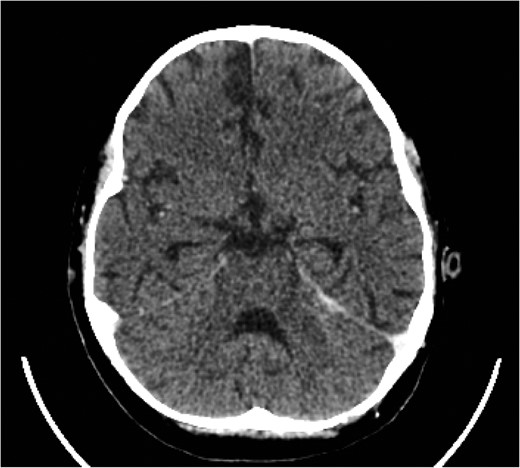

CT of the head with contrast revealed opacification of the left mastoid air cells with multiple ring enhancing abscesses throughout the brain, the largest of which in the left cerebellar hemisphere, measuring 4.4 × 2.9 cm in maximal axial dimensions (Fig. 6). There was non occlusive thrombus of the left internal jugular vein and superior sagittal sinus (Fig. 7). A repeat CT thorax revealed persisting left lung abscesses, a left sided collection and a new post drainage large, right-sided haemothorax.

CT scan of head with contrast revealed multiple ring enhancing lesions within the brain, opacification of the left mastoid air cells and thrombus within the superior sagittal sinus and left internal jugular vein.

The cerebellar brain abscess was drained surgically, with pus sent for microscopy and culture. This returned gram negative coliform organisms and pus cells. The antibiotic therapy was modified to account for the new microbial sensitivities. The appearances of both the brain and chest improved over the next 10 days with complete resolution of the intracerebral abscesses and thrombosis (Fig. 8). There was a slower resolution of the chest. The patient was discharged from our institution after 16 weeks.

Eventual complete resolution of the brain abscesses and sinus/ IJV thrombosis.